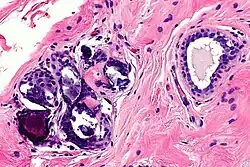

Mechanical and enzymatic (ME) methods are the most common isolation methods, although there is no standard method.[11] Accordingly, Glass and Ferretti proposed one of the ME methods which is to apply tumescent-assisted liposuction using a mechanical or ultrasound-assisted liposuction cannula. Through liposuction, the fat sample is digested by enzymatic activities of collagenase or trypsin in Dulbecco's modified Eagle's medium (DMEM). The resultant tissue suspension undergoes incubation and agitation at around 37 °C and is filtered through a strainer to remove unnecessary debris. The cell pallet left after centrifugation is the SVF, which is seeded on the plate after the second suspension with bovine calf serum, 1% penicillin or streptomycin, and L-glutamine. The adherent properties of ADSCs on the plate allow for their isolation,[12] but due to the inconvenience of isolating the pure ADSCs, a cell-assisted lipo-transfer (CAL) is more commonly used. CAL transforms poor ADSCs into enriched ADSCs by mixing SVF isolate and aspirated fat.[13] The efficacy of CAL was proven by the increased survival rate of autologous breast augmentation when introduced around 270 ml for each breast.[14]